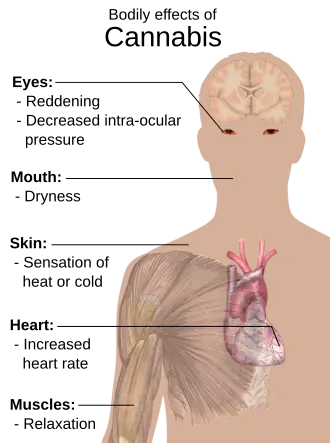

Cannabis has been cited as the sole cause of at least some traffic fatalities.[14][15] After cannabis legalization in Colorado, traffic fatalities in which cannabis was at least partly-responsible increased to 94 in 2014, a not-insignificant number compared to alcohol-related traffic fatalities for that year (170 fatalities).[14] Cannabis does impair judgment, motor coordination, and reaction time,[14][16][17] and its effect on impairment is either additive or synergistic with alcohol.[17]

Cannabis has been associated with at least 7 cases of heart attacks in different people (at least 4 of whom had normal coronary vasculature) and possibly some deaths, and cannabis is known to have several vascular effects that may be causative (e.g., tachycardia, hypertension, bradycardia, and hypotension).[18][19][20][21][22]

Cannabis treatment for intraocular pressure from glaucoma is widely cited as effective, particularly because the first authorized usage of medical marijuana since its criminalization was based on a court case by Robert Randall in 1976.[29] There is some supporting scientific evidence that cannabis is efficacious for at least some types of glaucoma, based on small studies on humans. The effect on intraocular pressure is relatively brief, and there are other pharmaceutical treatments available for glaucoma that have been tested for safety and efficacy.[30][31] The American Glaucoma Society[32] and the Canadian Ophthalmological Society[33] oppose medical marijuana usage for glaucoma treatment due to extensive adverse effects.[30]